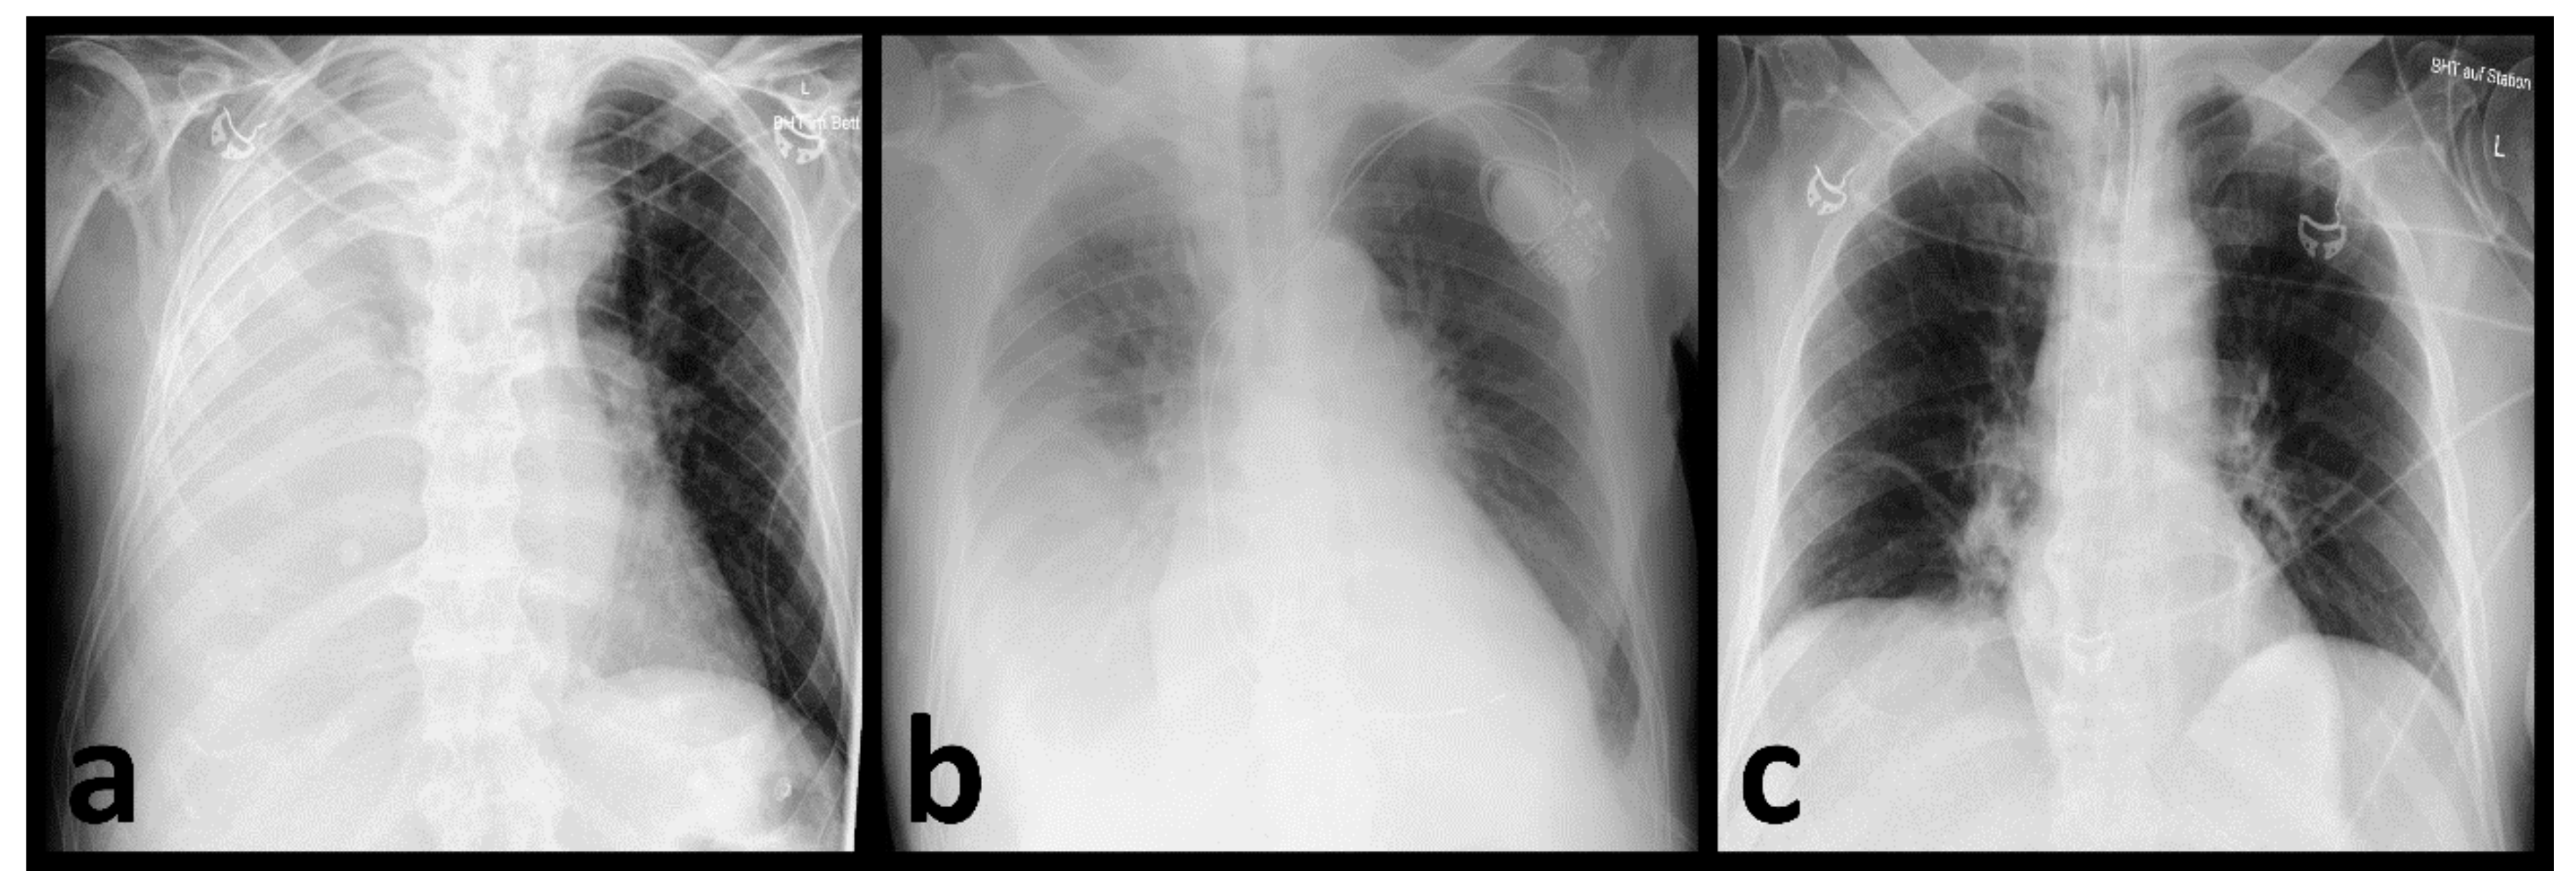

3.2. Identification of Pneumonia by Radiologists

3.3. AI-Based Diagnostic Performance